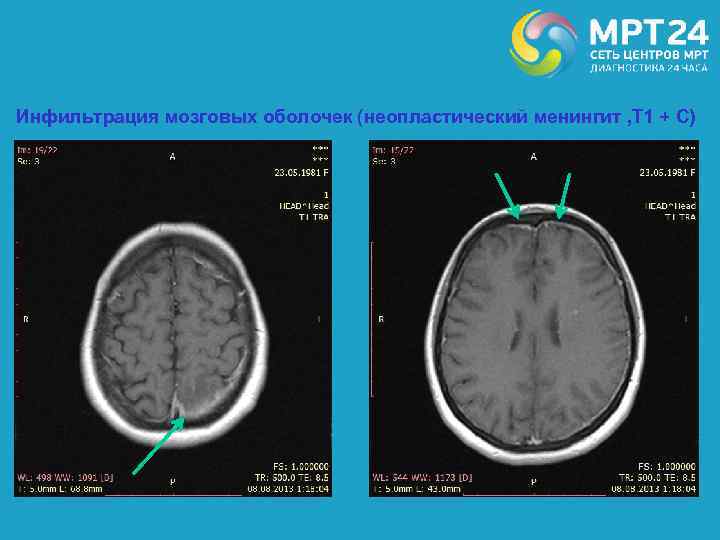

Повторное МРТ мозга через 3 месяца (FLAIR, Т 1 + С)

Инфильтрация мозговых оболочек (неопластический менингит , Т 1 + С)